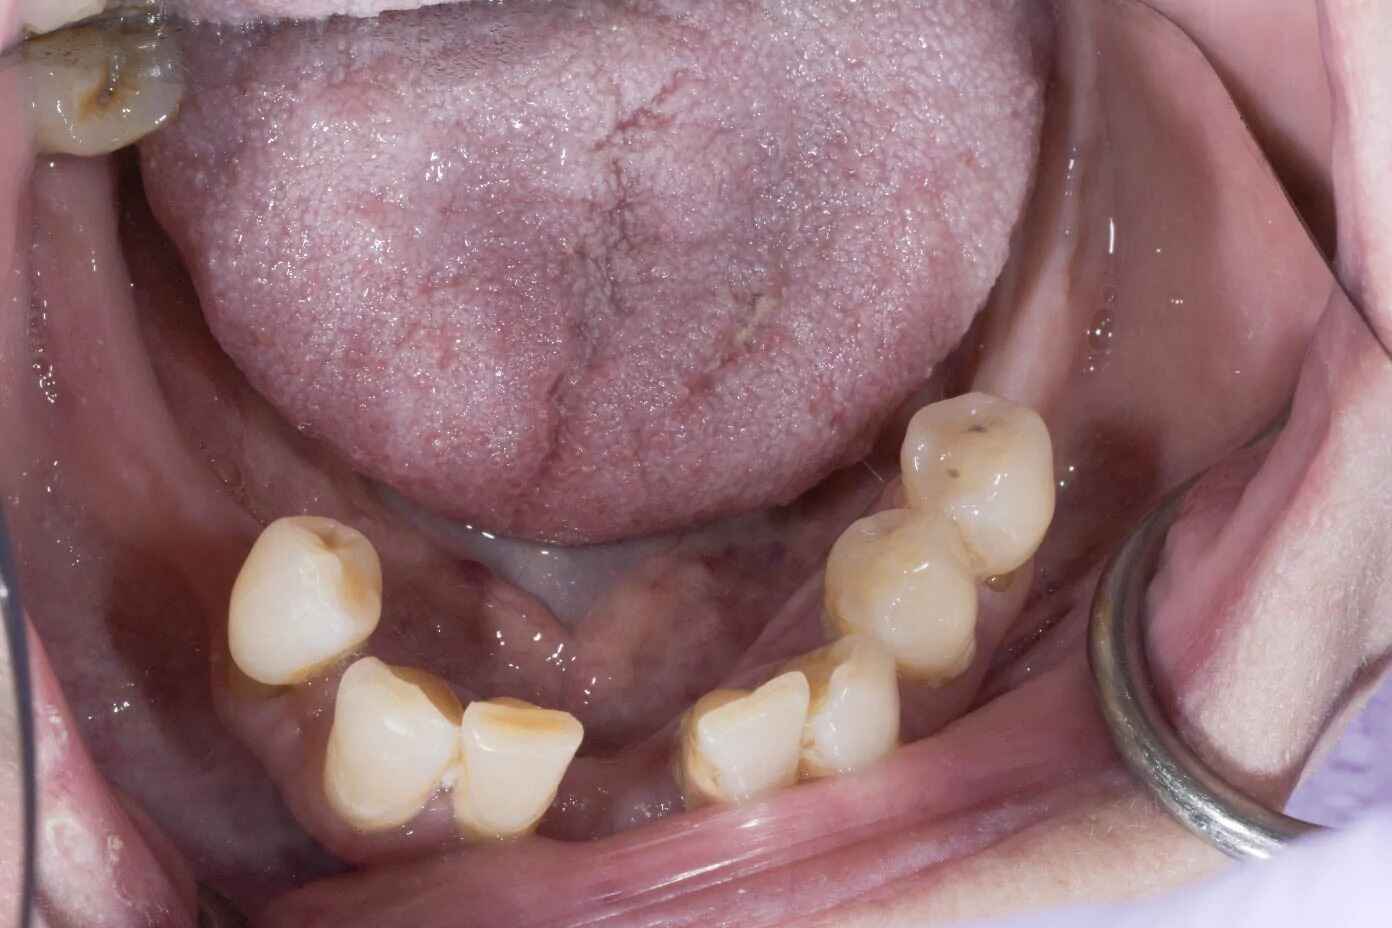

Jill’s Procedure

Jill needed a full mouth rehabilitation of dental implants and tooth crowns.